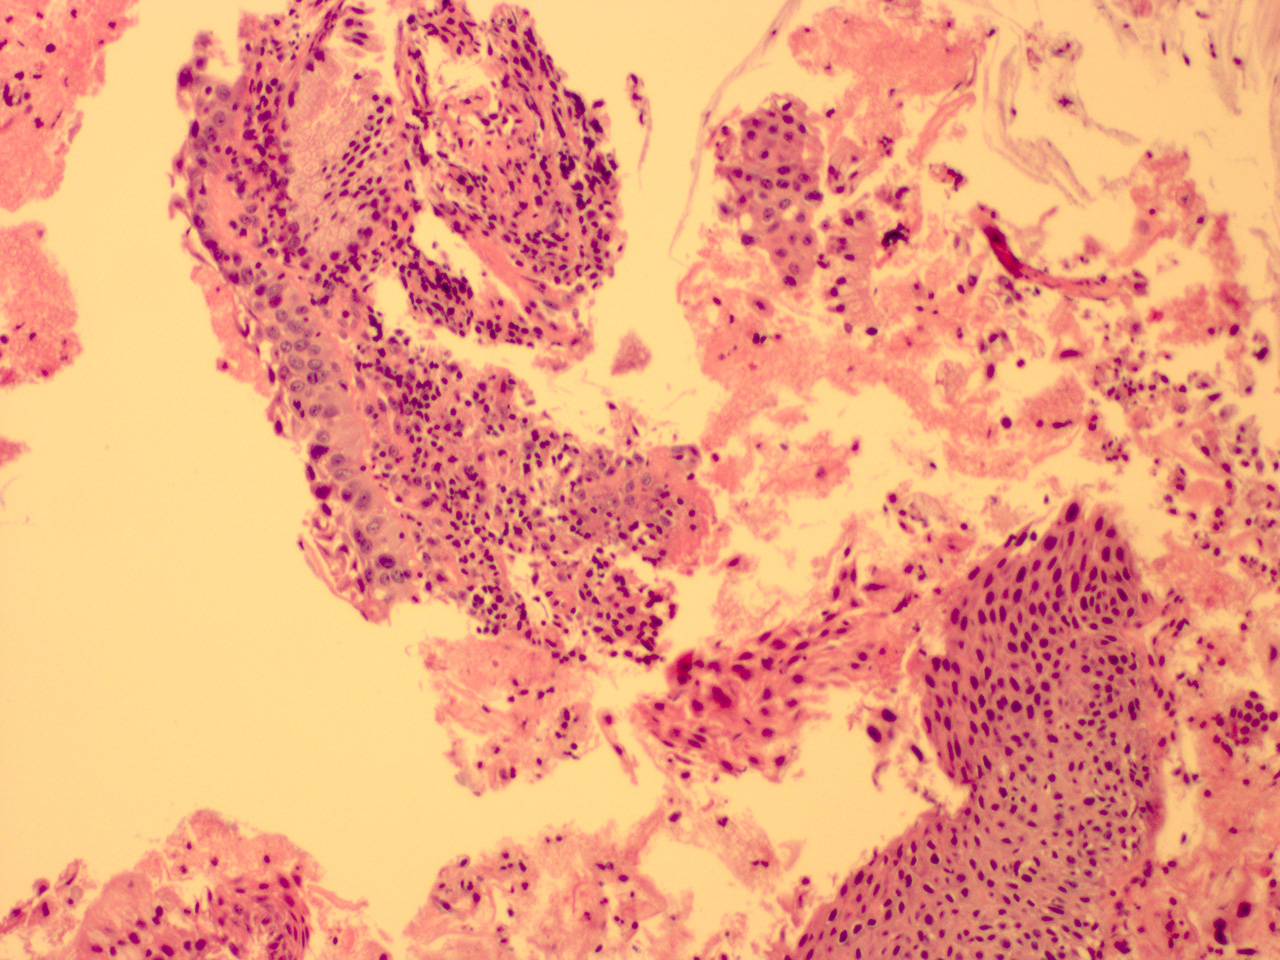

![]() Case 4

Soft Bx CIN 3

10x - Low Power |